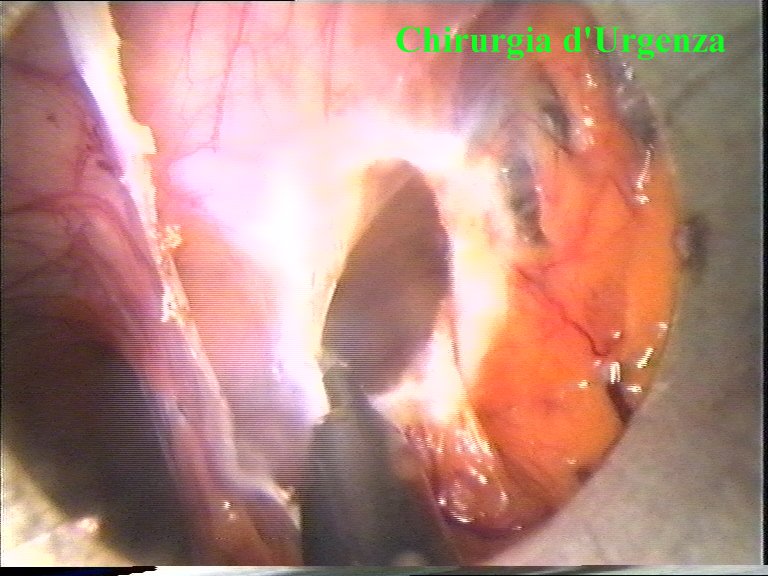

Figura 2

E’ raffigurato un quadro simile al precedente. Le aderenze sono maggiormente distese dall’aumento della pressione del pneumoperitoneo.